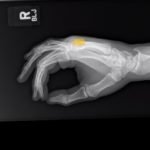

Significant findings:

A two-view radiograph of the right hand was obtained which revealed a dorsal dislocation of the distal fourth and fifth metacarpals (see red and blue outline, respectively) with a concomitant fracture of the distal fifth metacarpal (see yellow line) and avulsion fracture of the lateral aspect of the hamate (see green line). After reduction the fourth and fifth metacarpal dislocations are resolved; however, the distal fifth metacarpal fracture (yellow line) and avulsion fracture of the lateral aspect of the hamate (green line) are still visible.